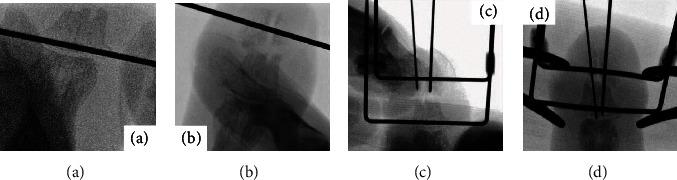

The nonunion of distal phalangeal communized fracture is relatively rare in hand fractures. However, if it occurred, the surgical treatment is quite difficult because of small piece of fragmentations. We developed a new fixation method that involves the insertion of two wires and external wire compression fixation using a metal clamp. The aim of this technique was to increase the compression force between fragments and rigidity of conventional percutaneous Kirschner wire fixation. Here, we present a patient with the nonunion of distal phalangeal communized fracture who was satisfactorily treated with open reduction and percutaneous interfragmentary compression fixation with a linking external wire fixator (the Ichi-Fixator system). Such a treatment that enables compression fixation for communized distal phalangeal fracture of nonunion will clearly boost bone healing. Linked external wire-type compression fixator (the Ichi-Fixator system) enables enhanced security of fixation and facilitates the bone healing.

指骨远端粉碎性骨折不愈合在手部骨折中相对少见。然而,如果发生这种情况,由于骨折碎片较小,手术治疗相当困难。我们开发了一种新的固定方法,即插入两根钢丝并使用金属夹进行外部钢丝加压固定。该技术的目的是增加骨折碎片之间的压缩力以及传统经皮克氏针固定的刚度。在此,我们报告一例指骨远端粉碎性骨折不愈合患者,采用切开复位并用连接外部钢丝固定器(Ichi固定器系统)进行经皮骨折块间加压固定,治疗效果满意。这种能够对不愈合的指骨远端粉碎性骨折进行加压固定的治疗方法将显著促进骨愈合。连接外部钢丝式加压固定器(Ichi固定器系统)可提高固定的安全性并促进骨愈合。